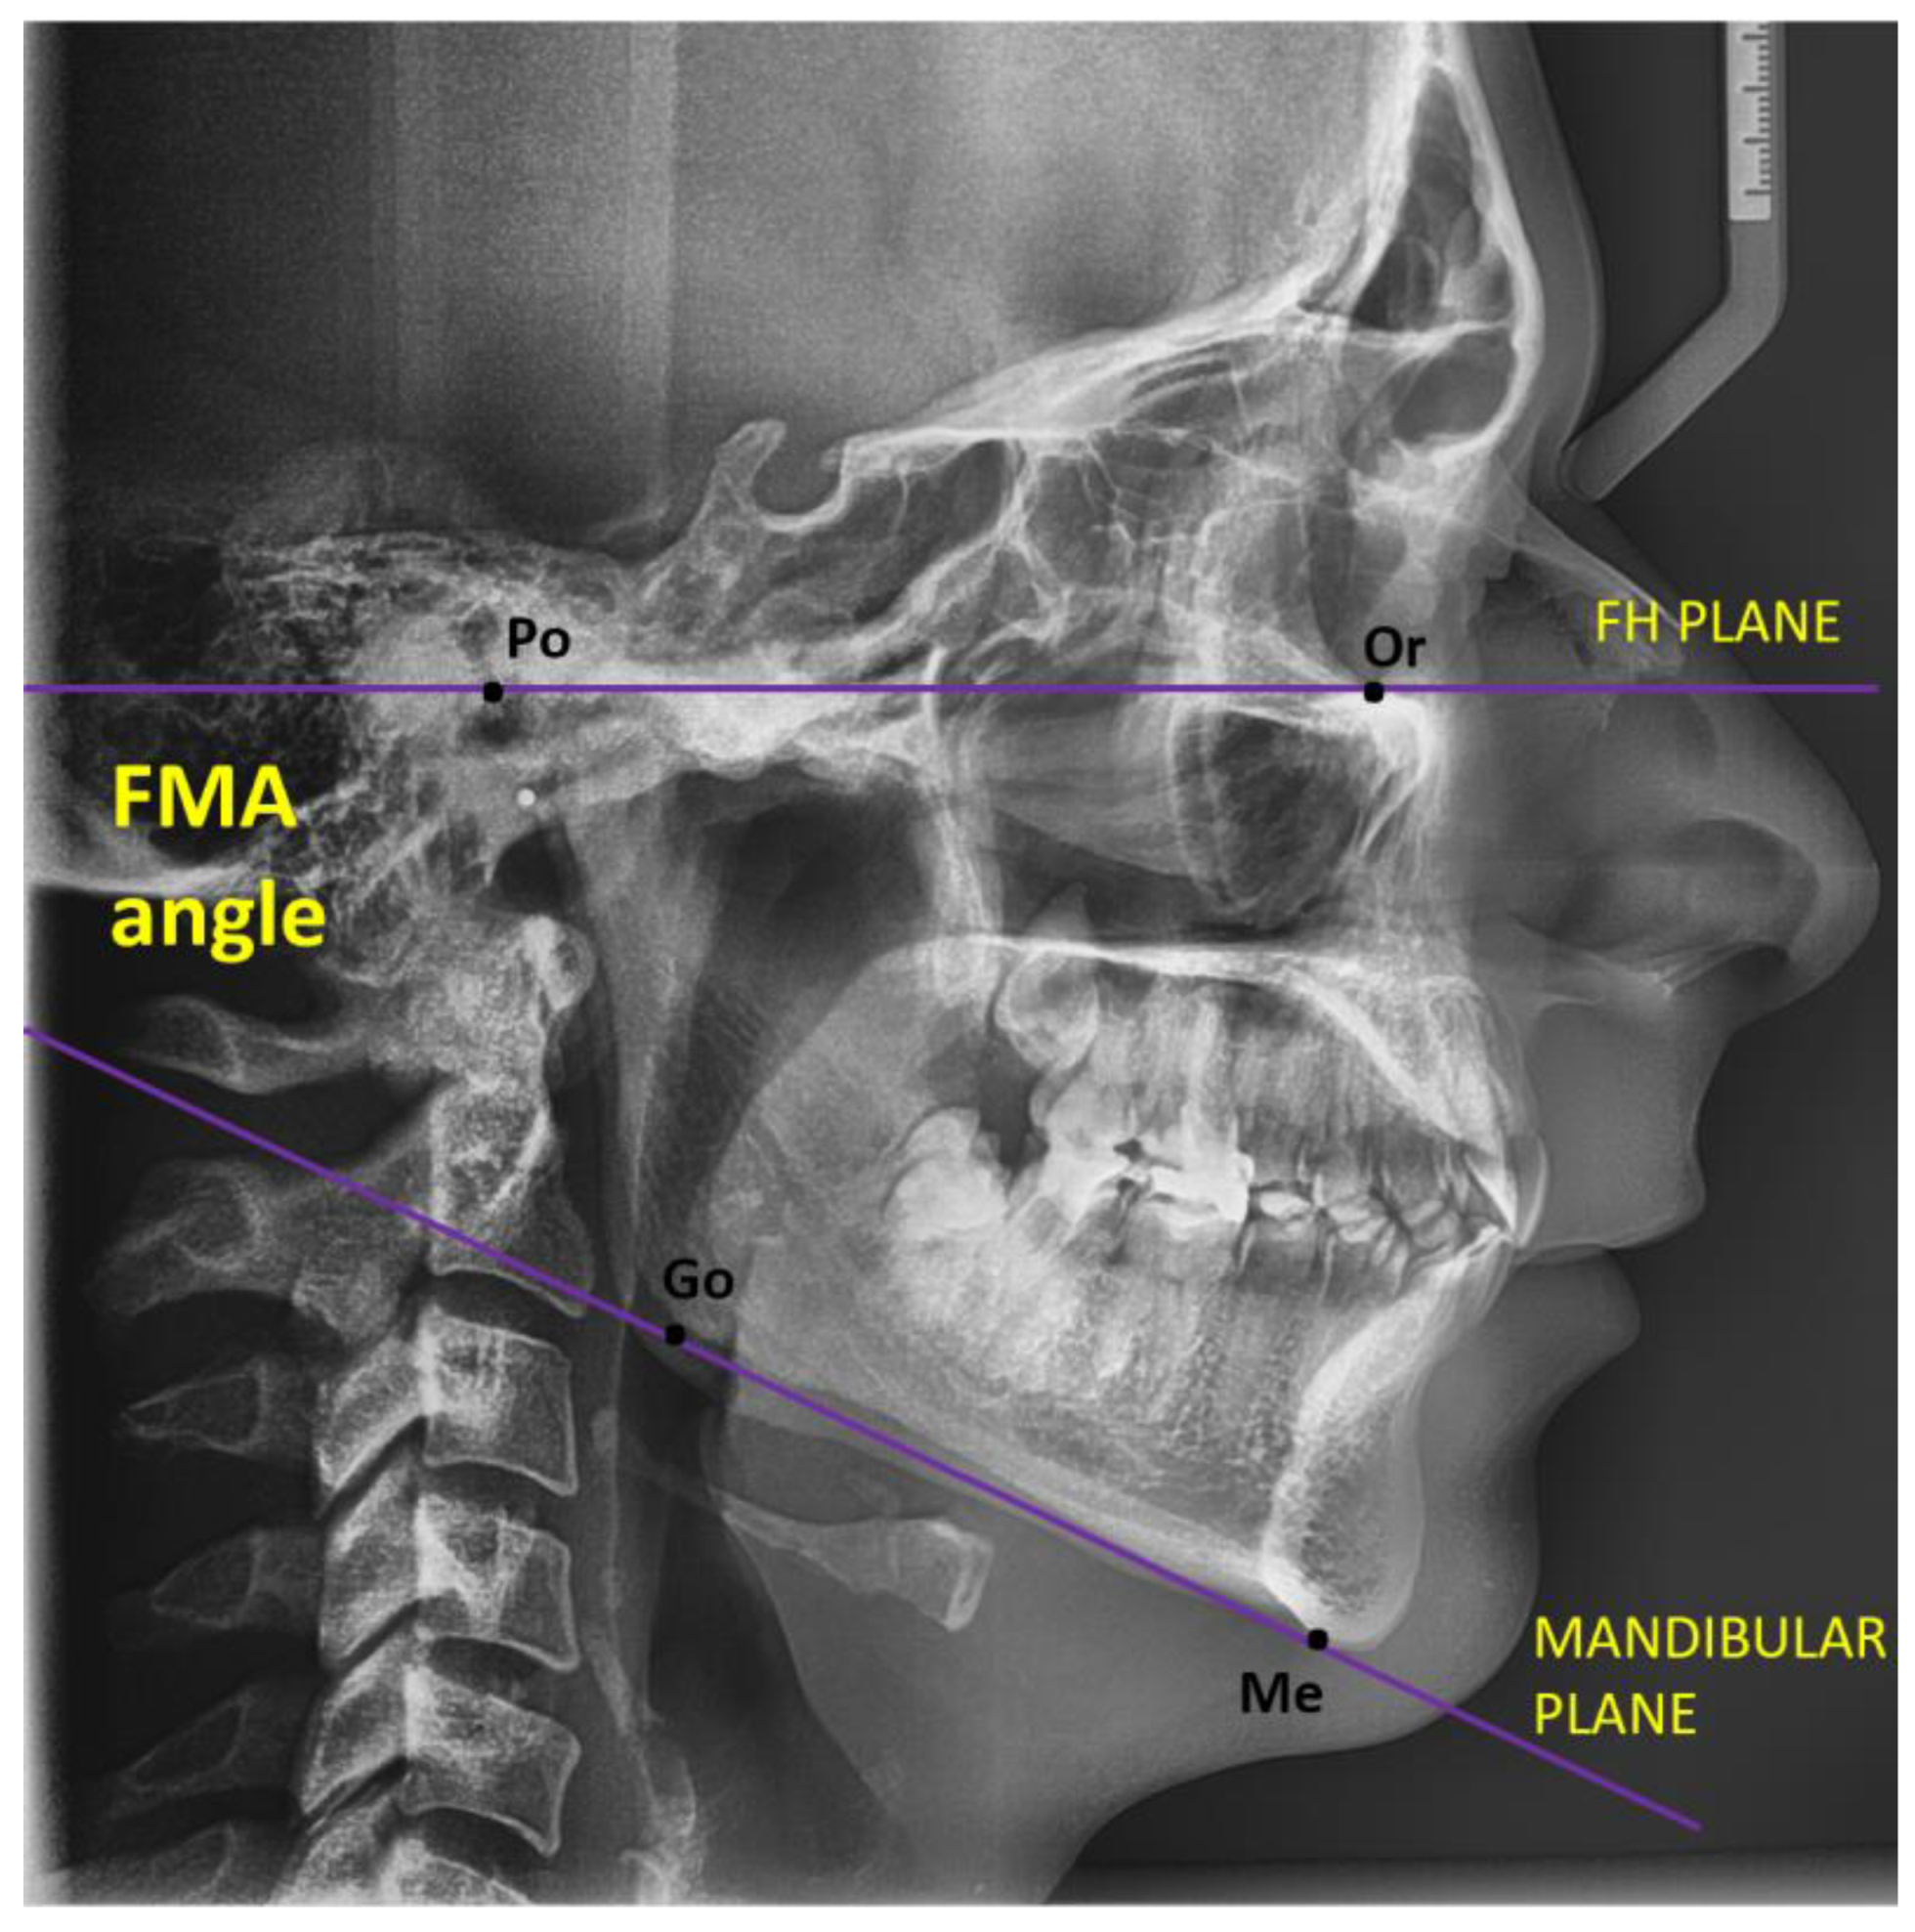

2.1.1. Digital Lateral Cephalometric Measurements and Protocol